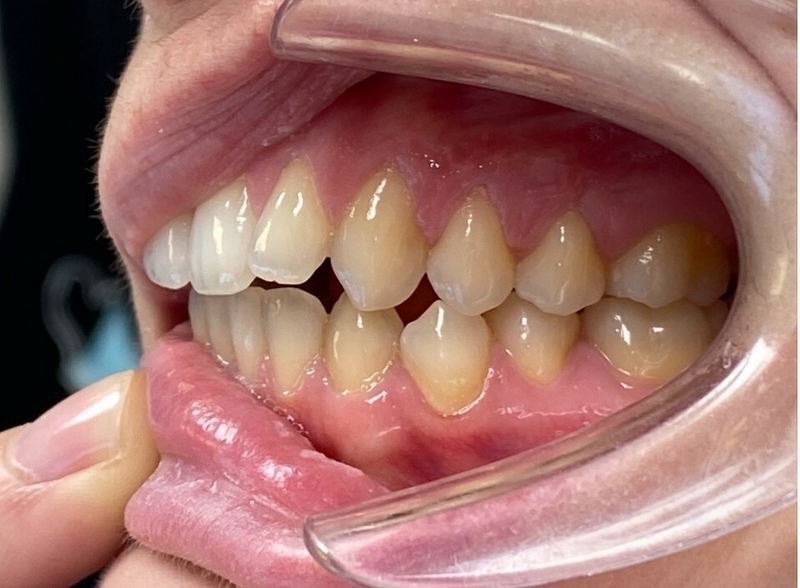

Cas 2 - Orthodontie par aligneurs invisibles

Avant